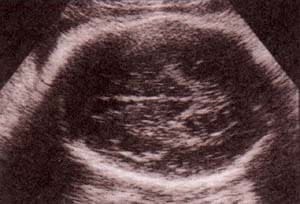

fig. 61. anencefalia. 14 semanas.ausencia de calota observándose un tejido cerebrovascular expuesto. no hay masa encefálica. |